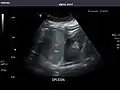

Spleen: Normal in size.

Spleen